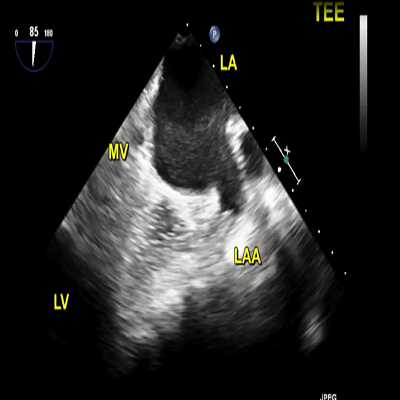

TEE: left atrium enlarged

604 KB

TEE: spontaneous echo contrast in the dilated LA

730 KB

TEE: thrombus in the LAA

758 KB